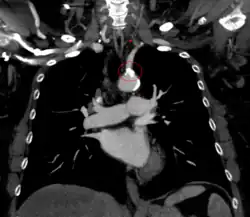

Additional images